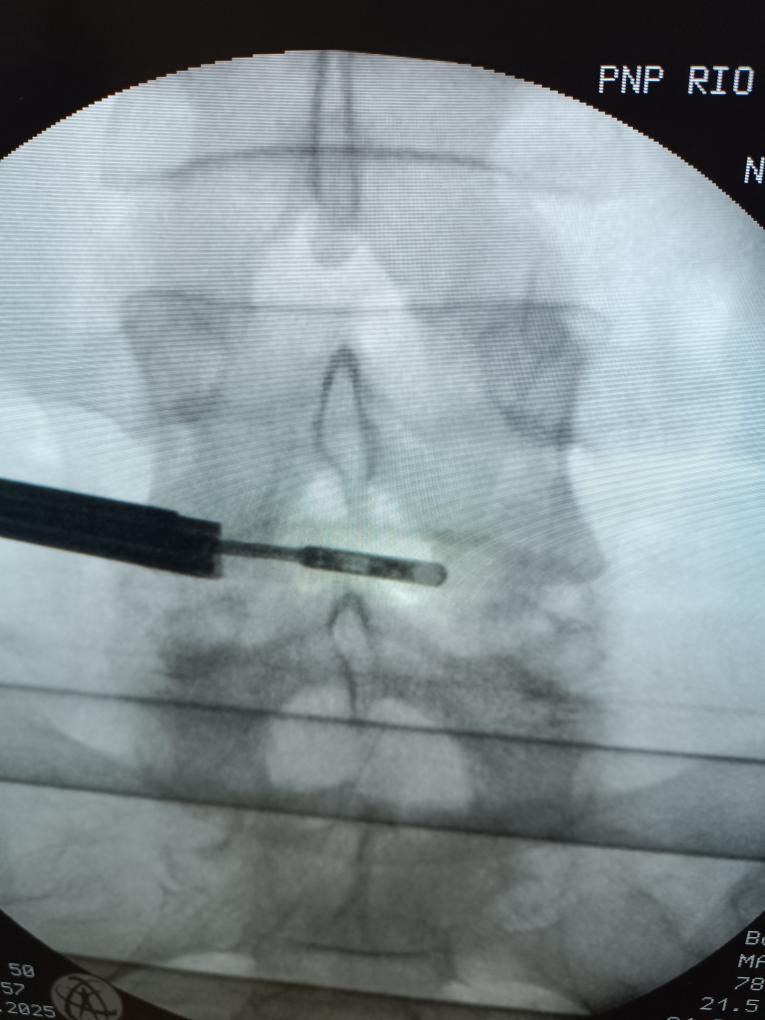

Διεγχειρητική απεικόνιση διαδερμικής μικροδισκεκτομής.